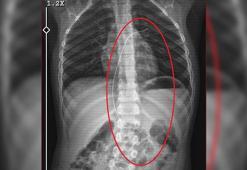

Salatalık yutunca rahatsızlandı; 3 yıl önce vücudunda 18 santimlik kateter unutulduğu ortaya çıktı

Salatalık yutunca rahatsızlandı; 3 yıl önce vücudunda 18 santimlik kateter unutulduğu ortaya çıktıŞırnak'ta piknikte salatalık parçası yuttuktan sonra öksürük ve kusma şikayetleriyle hastaneye götürülen Aram Devran Ötün’ün (6), 3 yıl önce Stevens- Johnson sendromu nedeniyle tedavi gördüğü sırada damar yoluna takılan 18 santimetrelik kateterin vücudunda unutulduğu ortaya çıktı. Öğüt, 5,5 saat süren riskli bir ameliyatla kateterden kurtuldu.